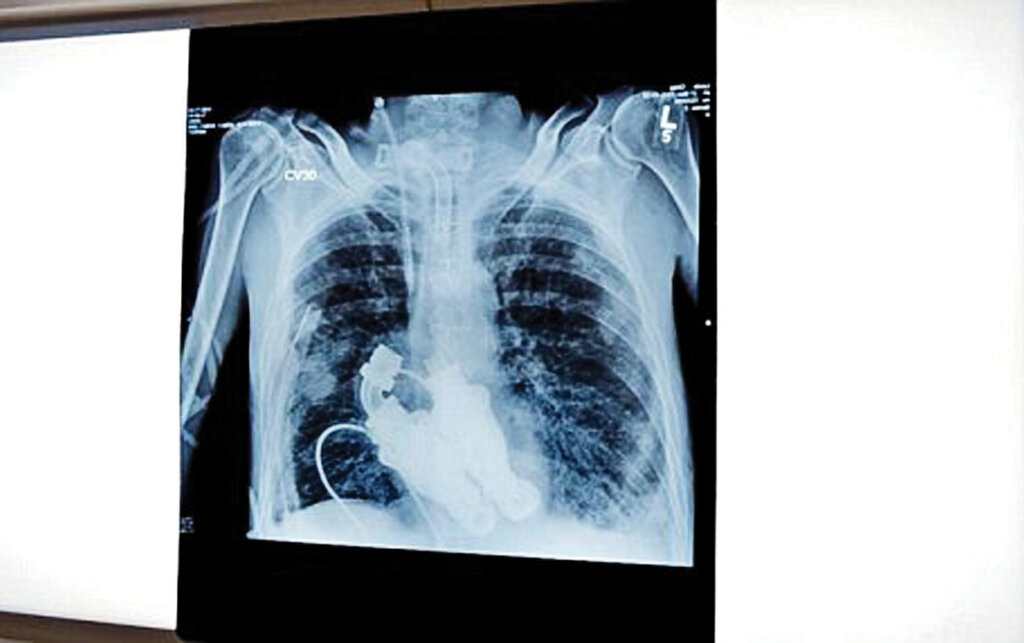

این دو پزشک به خانواده کرگ پیشنهاد دادند که با خارج کردن قلبش، وسیلهای در بدن او کار بگذارند که باعث شود خون در بدن کرگ البته بدون هیچگونه ضربانی جریان داشته باشد و به این ترتیب بود که کرگ لوئیس زنده ماند. این اتفاق آنقدر در دنیای پزشکی مهم بود که «جرمی زاگار» مستندساز معروفی که در سال ۲۰۱۰ کاندیدای دریافت دو جایزه «امی» شد فیلمی از دنیای شگفتانگیز نخستین انسان بدون قلب با تمام جزئیات آن ساخته است.

وسیلهای که به جای قلب در سینه کرگ کارگذاشته شد شبیه توربینی است که نقش موتورهای چرخش سریع خون را دارد و برای اینکه این وسیله بتواند خون را در بدن به جریان بیندازد مجهز به بخشهایی شبیه به تیغههای پهن است.

البته بیماران دیگری از جمله دیک چنی معاون رئیسجمهور سابق آمریکا هم، وسیلهای شبیه به چیزی که به جای قلب در سینه کرگ کار گذاشته شد دارند با این تفاوت که این وسیله روی یکی از بطنهای آنها کار گذاشته شده و کمک میکند تا قلب ضربان داشته باشد و بتواند خون را در بدن به گردش درآورد.

کرگ در بخش مراقبتهای ویژه بستری بود. هریک از پزشکان به نوبت گوشی طبی را روی سینه کرگ میگذاشتند اما هیچ صدای ضربان قلبی به گوش نمیرسید و تنها صدایی مثل وزوز از سینه کرگ به گوش میرسید. گوشی طبی به لیندا همسر کرگ داده شد. او درباره این لحظه هیجانانگیز و باورنکردنی میگوید: «من با دقت گوش کردم، فقط صدای وزوز میآمد. باورنکردنی بود. او هیچ ضربان قلبی نداشت. چون هیچ قلبی نداشت.»